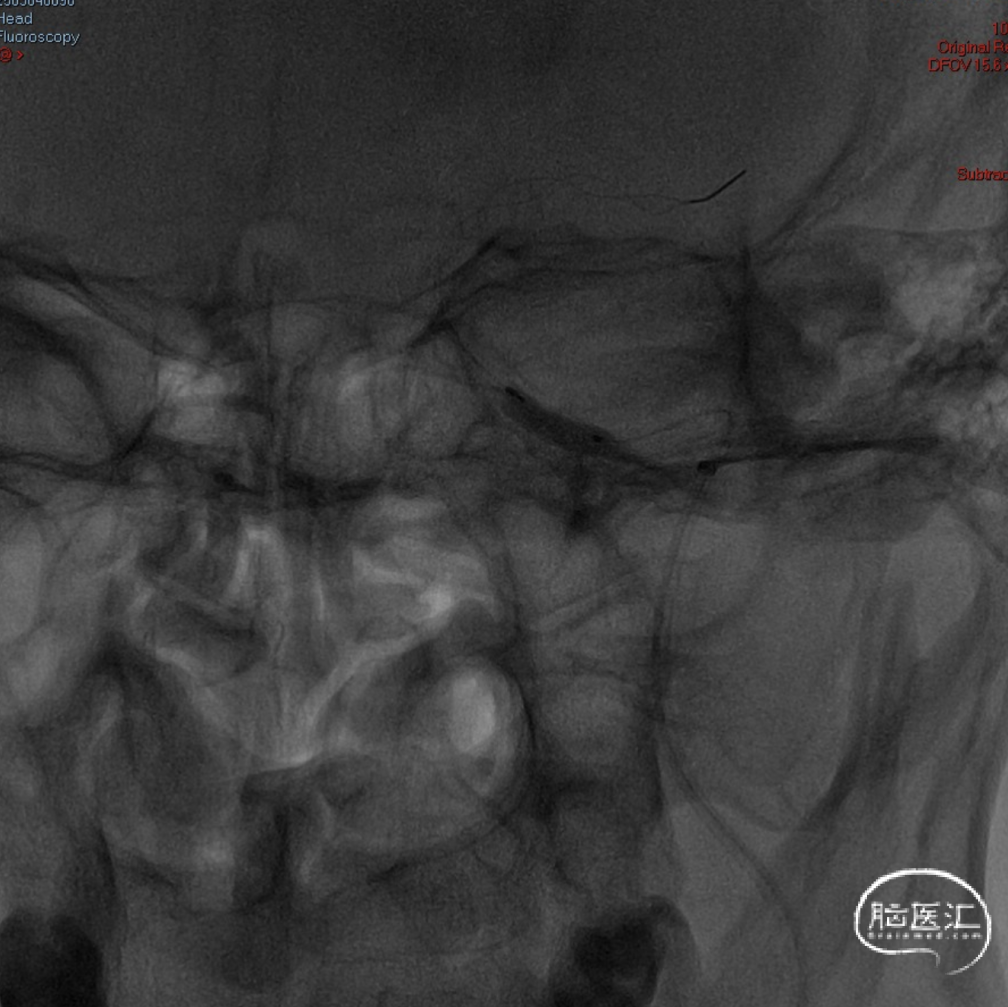

沿4.0×30mm Syphonet®取栓支架输送导丝送入3.0×12mm SacSpeed®球囊扩张导管,自C1-C7段分次扩张,每次释压后跟进中间导管至C5段,复查造影显示血流通畅。

造影提示C5-C6段仍有残余狭窄。于是利用SacSpeed®球囊扩张导管收回部分Syphonet®取栓支架,在狭窄处直接扩张。

撤回SacSpeed®球囊扩张导管,复查造影。

· 沿5F Tethys®中间导引导管送入3.5-5.5mm×300cm 保护伞于C5段释放,同轴送入Sterling 4.0mm×30mm 球囊扩张导管并覆盖C1段最狭窄处理,以14atm扩张维持约5秒并迅速释压,观察约1分钟患者心率及血压无明显变化,且意识及肢体功能无明显改变,复查造影示C1段狭窄较前明显改善。

· 撤出球囊导管送入7.0×40mm 自膨式支架,在路图及造影下定位,于狭窄处释放,再次造影提示C1段残余狭窄<10%,保护伞处近端造影剂充盈欠佳。